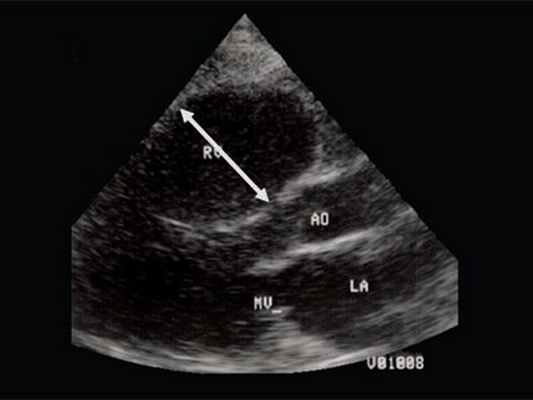

Характерными особенностями выраженной объемной перегрузки правого желудочка являются дилатация желудочка, при которой толщина миокарда не превышает верхней границы нормы, увеличение правого предсердия, парадоксальный характер движения межжелудочковой перегородки и увеличение амплитуды движения трикуспидального клапана (рис. 2, 3).

Рис. 2. Длинная ось сердца. Объемная перегрузка правого желудочка при дефекте межпредсердной перегородки. Объем сброса крови превышает 200% МОС. Отмечается выраженная дилатация правого желудочка.